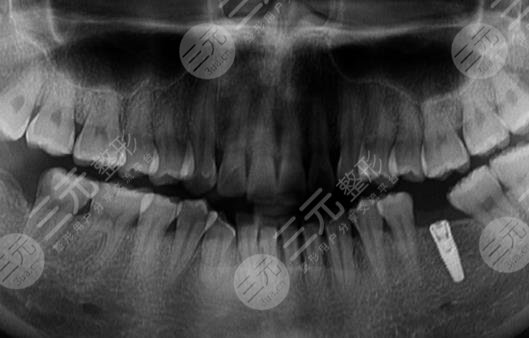

到医院进行面诊的时候,医生先让我咬了牙齿的模型,然后又拍了牙片,选择了牙齿的种植体,一星期之后,我来到了医院进行种植牙。整个种植牙的过程是很快的,而且因为打了局部mz也没有任何的感觉。大家现在可以看到我的种植牙是十分成功的,而且看上去十分的洁白,跟周围的牙齿形成了鲜明的对比。